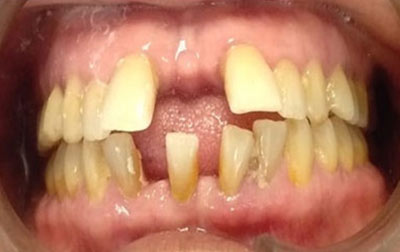

Smile makeover:

Radiating confidence through a beaming smile can truly uplift your spirits. A captivating smile holds significant sway in social and professional spheres, enhancing your overall appeal. However, numerous individuals refrain from revealing their teeth in public or photographs due to personal dissatisfaction. If you find yourself in this category, why not consider allowing us to assist you in attaining the smile you've always envisioned? Embark on a journey toward your ideal smile with our transformative smile makeover. A smile makeover transcends the mere resolution of dental issues as they arise. It constitutes a holistic plan to rejuvenate your smile, intricately tailored to complement your distinct facial features and aesthetic inclinations. The outcomes are nothing short of remarkable—both in terms of your visual transformation and the surge of newfound confidence you'll experience.